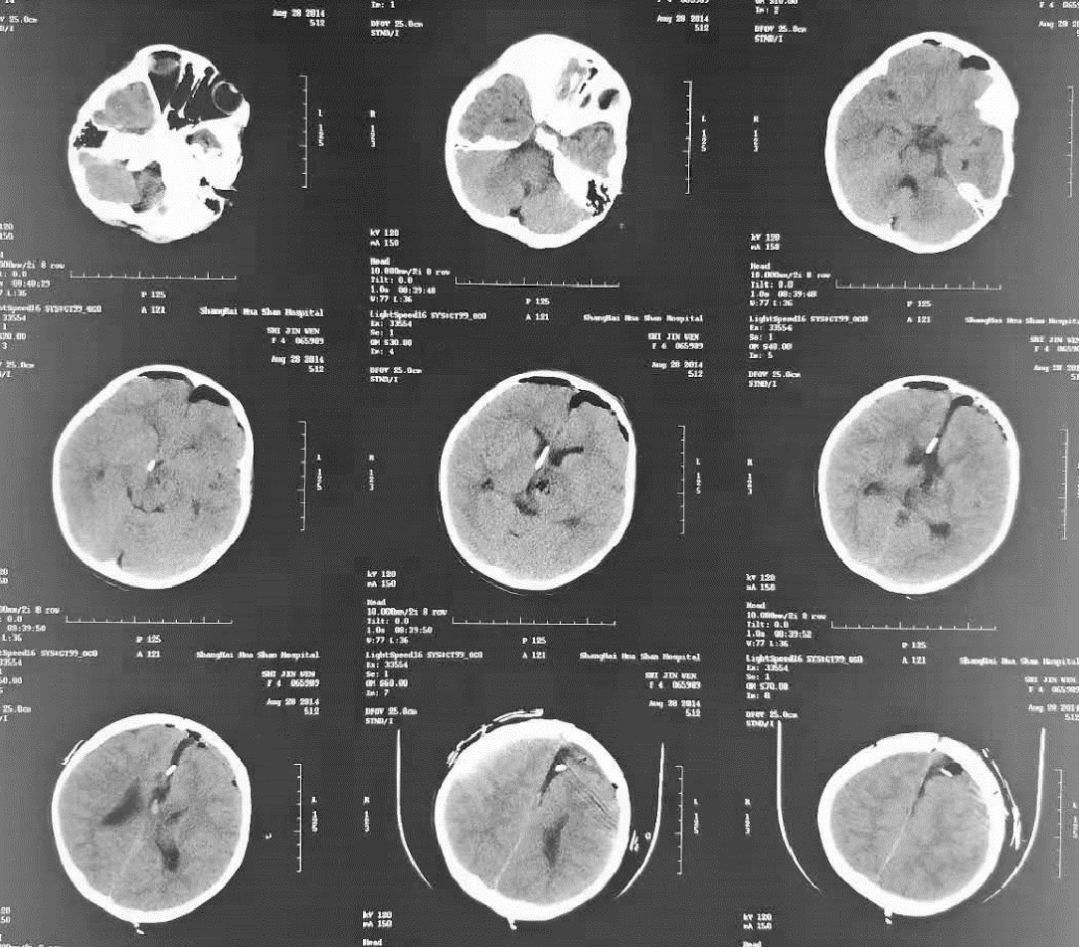

一样的丘脑血肿,不一样的治疗方法之二(副本)

术前ct:丘脑血肿破入脑室,急性脑积水.

2月28日复查头颅ct片,右侧丘脑血肿以及脑室内血肿全部清除干净,结果